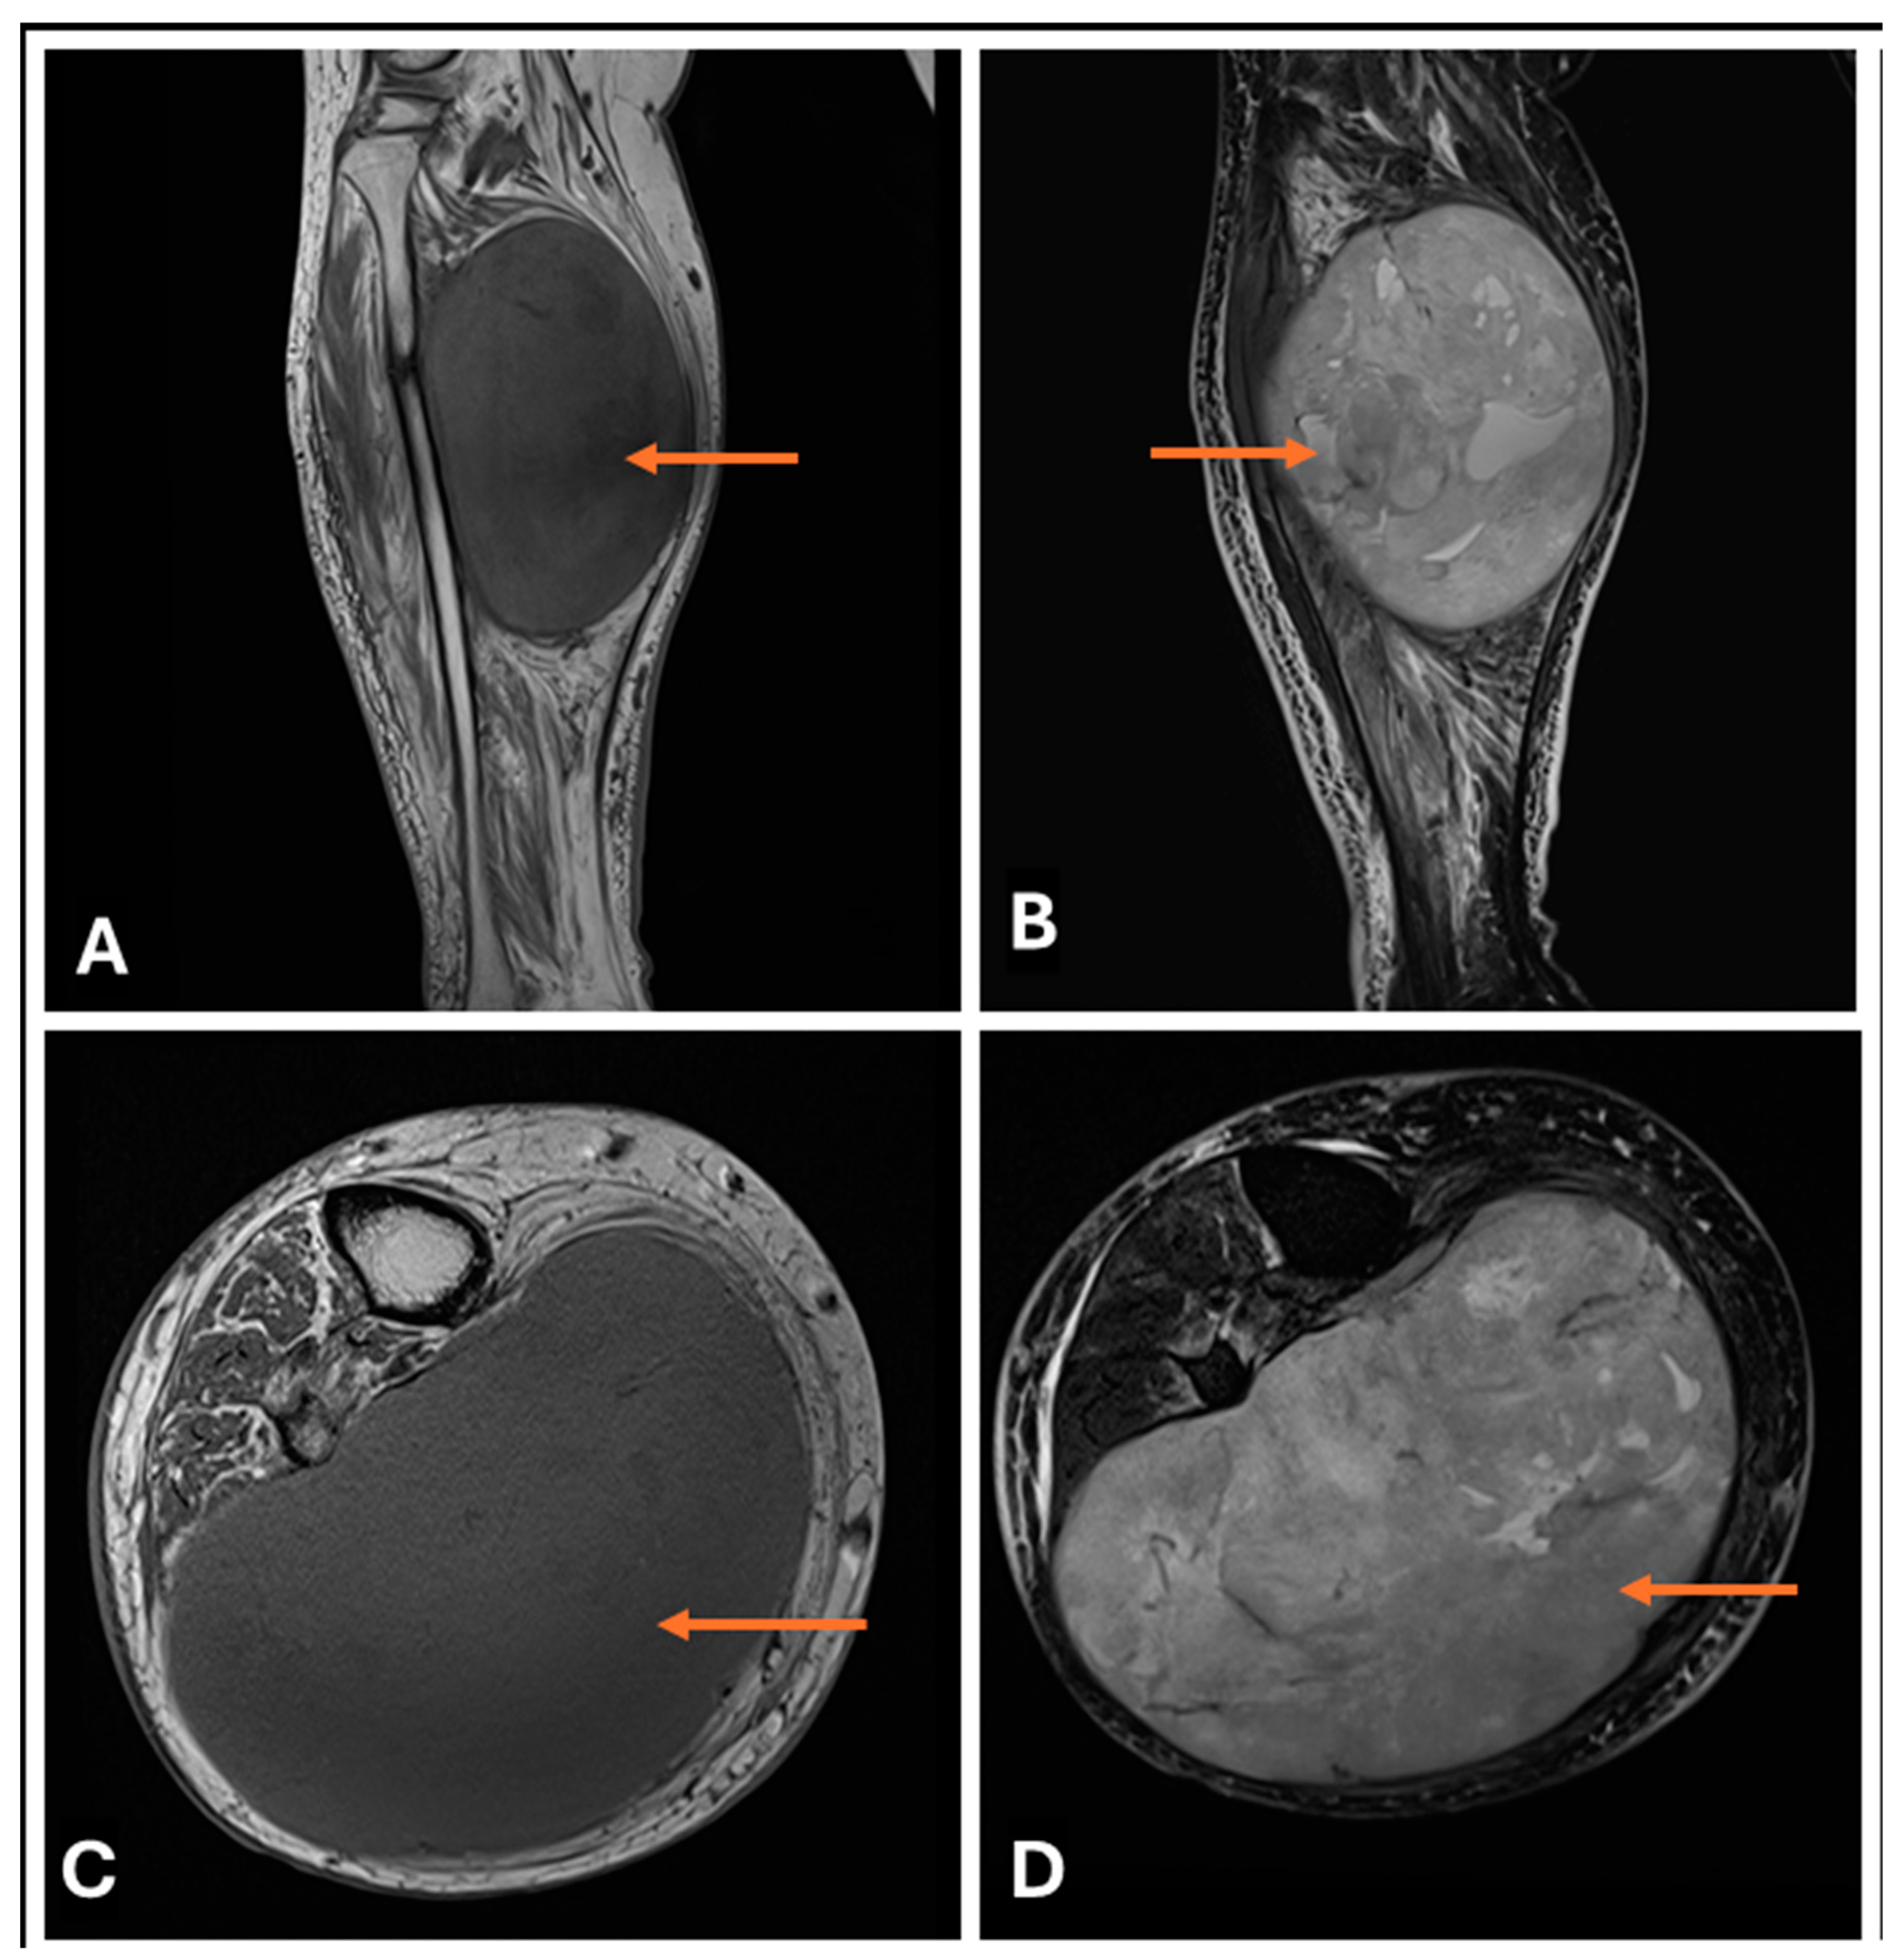

- Primary Sarcomas: Soft-tissue sarcomas are uncommon, accounting for just over 1% of adult malignancies. Synovial sarcoma, clear cell sarcoma, and epithelioid sarcomas are known to involve peripheral nerves. CT/MR reveals a large soft tissue mass with areas of necrosis or calcification and heterogeneous contrast enhancement. F-18 FDG uptake is useful for both tumor staging and treatment assessment (Figure 26, Figure 27 and Figure 28).